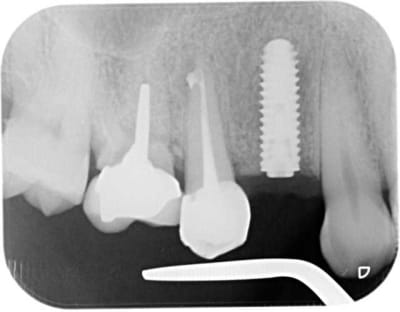

pour la forme et le fond pano avant retro à la pose et rétro aujourd'hui

prévu implant en 36 et l'endo de 15 avait été reprise avant pour être refaite simultanément je connais les critiques nonoliennes.

pour info déja trois cas similaires au maxillaire pas à la mandibule.

et c'est un axiom en 4*12 pas un krestal